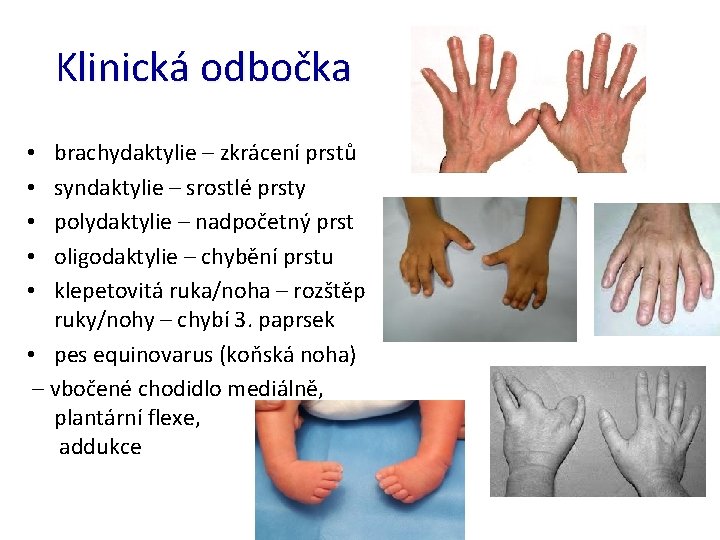

Klinická odbočka brachydaktylie – zkrácení prstů syndaktylie – srostlé prsty polydaktylie – nadpočetný prst oligodaktylie – chybění prstu klepetovitá ruka/noha – rozštěp ruky/nohy – chybí 3. paprsek • pes equinovarus (koňská noha) – vbočené chodidlo mediálně, plantární flexe, addukce • • •